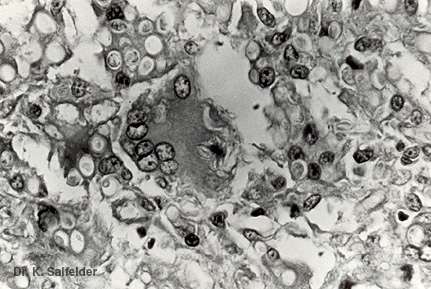

Abb. 10,4: Afrohistoplasmose

Zahlreiche Pilzzzellen sehen wie Vakuolen aus. In einer Riesenzelle ist ein Asteroidkoerperchen zu sehen, in dem man eine Pilzzelle nicht erkennt. HE-Faerbung